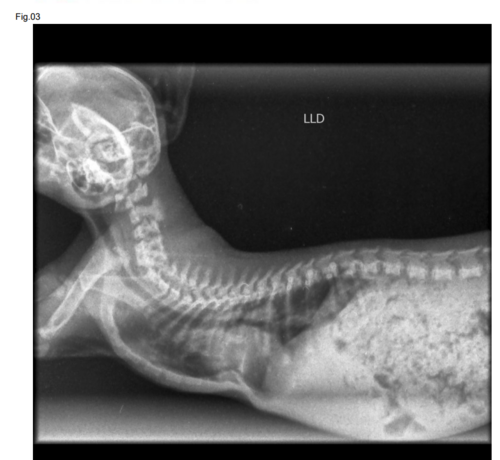

Meu nome é Bianca, estou criando essa vaquinha para poder inicialmente cobrir os exames do Jimin que tem apenas dois meses, e foi diagnosticado com uma doença rara chamada pectus excavatum. Preciso de ajuda com os custos dos exames e posteriormente com apoio para cirurgia, essa má formação congênita dificulta a respiração além do peito do animal ficar em formato de cone pressionando os órgãos do animal.Até o momento o quadro dele teve piora considerável e precisa de ajuda urgente com os exames para prosseguir com a cirurgia, qualquer valor ajuda.Segue imagens, e anexos do orçamento. Assim que tiver o custo da cirurgia compartilharei com vocês. Deus abençoe.